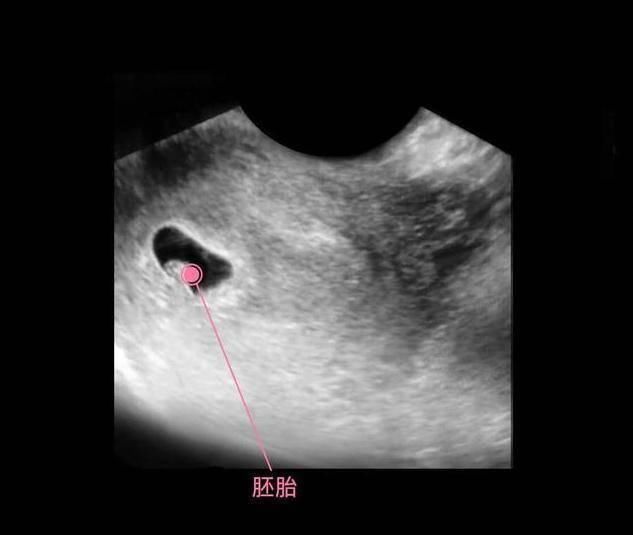

此时进入了第6周,胚胎已经具备了雏形,依稀可以卡到一个小人的形状,胚胎上下两面开始长出幼芽,将来发育成胎儿的手臂和小腿,面部器官开始形成雏形,不再是小海马的样子了。